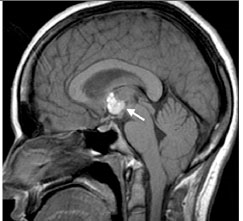

Sau khi thăm khám và điều tra bệnh sử, chụp cắt lớp vi tính có hoặc không có bơm thuốc cản quang đường tĩnh mạch là bước đầu tiên trong chẩn đoán các ca bệnh nghi ngờ ATSL thần kinh. CT não có hoặc không có thuốc cản quan sẽ cho thấy hình ảnh các tổn thương điển hình của ATSL đường kính nhỏ hơn 20mm và không có hình ảnh phản đứng giữa (no midline shift) là hình ảnh gợi ý cao cho thể ATTSL thần kinh (neurocysticercosis). Phần scolex, hoặc phần giác hút của ấu trùng cũng có thể nhìn thấy; đây là đặc trưng bệnh của ATSL thể thần kinh.

Hình 2. trên hình ảnh CT có nang của ATTSL thể thần kinh trong nhu mo não đặc | Hình 3. hình ảnh cộng hưởng từ cho thấy các nang của ATSL thể thần kinh trong nhu mô |

Số lượng, kích thước và vị trí có nang xuất hiện cũng như giai đoạn chu kỳ của nang sán, có thể xác định và có thể tác động đến việc quyết định điều trị. Các nang là các hình ảnh tổng thương dạng điểm có thể phát triển và tồn tại được, nang không bị thoái hóa. Các tổn thương dạng nang chỉ ra biến tính hoặc thoái hóa có một vài phản ứng viêm bao quanh. Cuối cùng, các nang hình thành calci hóa là một bằng chứng các nang đã tồn tại lâu có thể đã chết. Chăm sóc phải được tiến hành khi có thể còn nghĩ đến nhiều nguyên nhân khác (lao, bệnh ký sinh trùng khác, di căn từ nơi khác đến, hoặc ung thư nguyên phát của não hoặc hình ảnh abces não) khi một tổn thương tìm thấy trên phim chụp cắt lớp.

Hình ảnh trên phim chụp cộng hưởng từ cũng là công cụ hữu ích để chẩn đoán ATSL thể thần kinh và có thể tốt hơn cả chụp cắt lớp CT để phát hiện các thương tổn trong não tủy, trong cuống não, trong não thất. Việc áp dụng nó nên cân nhắc khi CT không chẩn đoán ra. CT và siêu âm là rất nhạy để phát hiện các tổn thương ATSL tại mắt và hệ cơ xương.